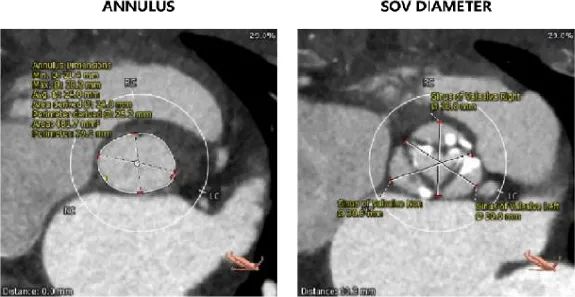

患者为 65 岁老年男性,主因“胸闷半年余”入院。患者既往无相关疾病史,半年前无明显诱因出现阵发性胸闷,夜间加重。行相关辅助检查后,心电图示“窦性心律;完全左束支传导阻滞;ST-T 段改变左心室高电压”;心脏彩超示“主动脉重度狭窄并大量反流、峰值流速 453cm/s、平均压差 50mmHg、估测主动脉瓣开放面积 0.6cm²;左心扩大,升主动脉扩张,室间隔及左室壁增厚;二尖瓣中量反流、三尖瓣少量反流;左室收缩功能下降;LVDD:62mm、LVEF:44%、PASP:50mmHg”。

左冠开口高度12.0mm,右冠开口高度17.8mm,左冠高度较低,根据瓦氏窦内径和瓣叶长度综合判断,左冠存在较高堵塞风险;左室腔增大,心室壁未见明显增厚。

因此,在手术策略的制定上,我团队根据患者瓣环平均径及周长数据(24.0mm/79.1mm),基于高钙化患者 down size 方案及降低冠脉封堵风险考虑,选择了 26mm TaurusElite 瓣膜进行植入。术中采用 22mm TaurusAtlas 球囊预扩后,显示轻微腰征,造影无渗漏,左冠开口显影不明显,验证了术前判断。遂预埋冠脉支架,行烟囱支架置入术。